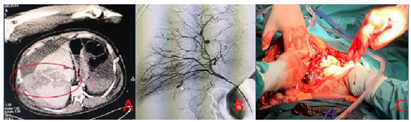

前方救援队员到达后,发现伤员病情仍不稳定,血红蛋白持续性下降,启动5G紧急医学救援系统,与后方专家组共同再次评估伤员。通过实时回传的超声图像,专家组发现伤员腹腔积液,疑似内脏器官破裂出血(图2)。建议先行选择性数字减影血管造影(digital substraction angiography,DSA)及血管栓塞控制出血后再行剖腹探查手术。但是现场不具备DSA能力,在当地有限的医疗资源下行剖腹探查手术风险极高。是否转运到后方医院进一步治疗成为一大难题。最终,前方队员与后方专家组讨论后决定,只有航空转运才能耗时最短,最大程度的保障伤员生命安全。抢救8 h后,伤员由AW119专业医疗直升机经过90 min的空中转运到达四川省人民医院急救中心。增强CT发现肝脏破裂(图3A),立即进行骨盆及肝脏DSA及选择性血管栓塞止血治疗(图3B),使得出血得到有效控制后即刻行损伤控制手术,术中证实肝脏破裂,行肝修补术(图3C)。手术后回到急诊监护室进一步复苏治疗,患者病情逐渐稳定。第2天,经过多学科专家团队评估后,认为伤员不稳定性骨盆骨折,失血量大,宜尽早进行机器人引导的微创骨盆骨折内固定术(图4)。